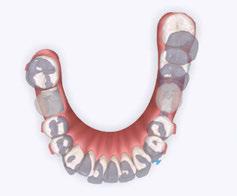

When used on mixed dentition, there will be a need to place extra buccal retention on the lower deciduous molars for the “C” clasps (Figures 12 and 13).

The evolution of printed biofriendly materials produced by Diamond Orthotic Lab for removable orthopedic development and facial pain has greatly improved treatment (Figures 14 and 15). These appliances are made of Type 12 nylon and are thermally active, making them easy to adjust with either hot or cold water.

Figure 12 and 13: Extra buccal retention on the lower deciduous molars for the “C” clasp